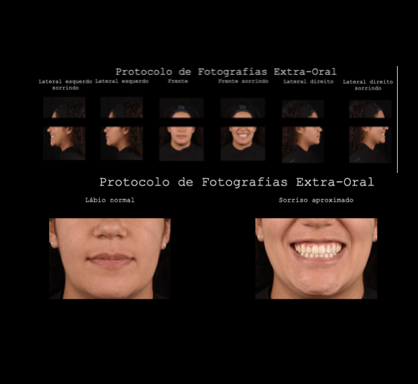

Protocolo Fotográfico

Podem ser feitas fotos artísticas, extra-bucal e/ou intra-bucal